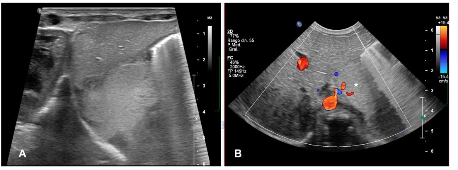

Ultrasound has a limited role in postnatal assessment due to the presence of air in the lungs, which hampers the visualization of deep structures, however, it remains useful in monitoring infradiafragmatic sequestrations.